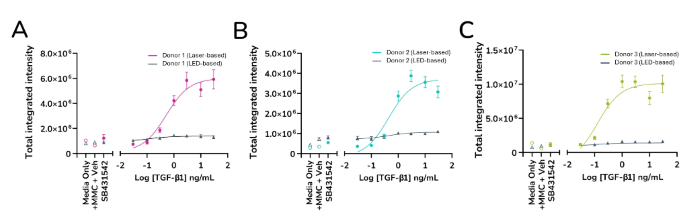

Enhanced sensitivity and rapid screening

When assessing the effectiveness of anti-fibrotic drugs, the HTHS FMT assay is extremely sensitive to detecting subtle variations in the expression of fibrotic markers. Compared to LED-based imaging, laser-based α-SMA expression imaging and quantification produces a "steeper" dose-response curve with a larger area under the curve, resulting in an assay with higher overall sensitivity.

- Compared to LED-based imaging, laser-based imaging has a higher sensitivity and can detect more subtle changes in the expression of fibrotic markers

- Faster imaging and reduced analysis times allow for the quick screening of numerous compounds

Quantified expression levels of α-SMA from ImageXpress Confocal HT.ai vs ImageXpress Pico. Data from three healthy human lung fibroblast donors (A, B & C). Image Credit: Newcells Biotech

The HTHS assay has been demonstrated to produce a more sensitive dose-response curve for measuring extracellular collagen I deposition and other ECM proteins, much like it does for measuring α-SMA expression. This makes it possible to screen for anti-fibrotic compounds using more predictive datasets.